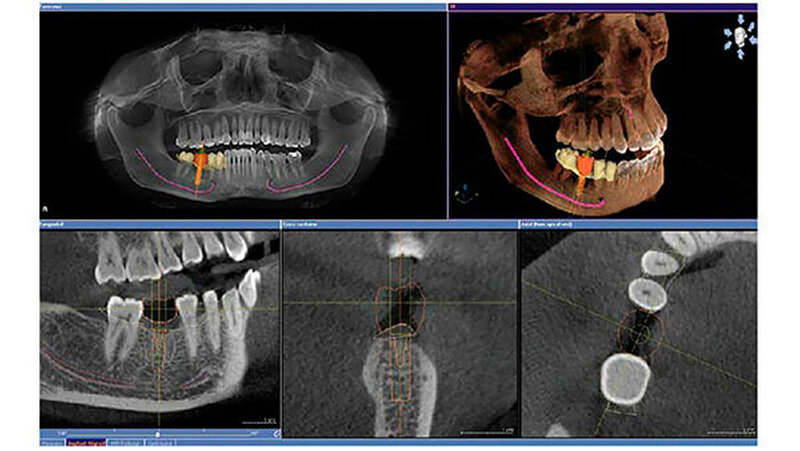

Die Investition in einen digitalen Volumentomografen liegt mit rund 70.000 Euro etwa doppelt so hoch wie bei Top-2-D-Geräten. Die Aufnahmen erleichtern fast jede Diagnose oder Behandlung - von der Wurzelspitzenresektion über den lokalen Knochenaufbau bis hin zum Sinuslift. Fortgeschrittene Systeme schaffen auch die Anbindung an die geführte Chirurgie (Bohrschablonen), teilweise sogar ohne die Notwendigkeit von Abdrücken oder Gipsmodellen. Dadurch wird die Entwicklung von einer primär am Knochenangebot orientierten zu einer von der Prothetik her geplanten implantologischen Behandlung befördert.

Bei der vorstehend skizzierten volldigitalen Herangehensweise ist nicht einmal eine Röntgenschablone nötig. Klassischerweise muss sie im Labor aus einer konventionellen Abformung hergeleitet werden - über das Meistermodell, eine Wachsaufstellung, eine Tiefziehschiene mit dem prothetischen Vorschlag, montiert auf eine Aufbissplatte. Erst dann erfolgen das 3-D-Röntgen und die eigentliche Implantatplanung.

Für jeden dieser Prozesse stehen heute mehrere Wege zur Bohrschablone offen. Einer davon führt über zentrale Dienstleister: Der Zahnarzt schickt seine Planungsdaten und die 3-D-Röntgenaufnahme dorthin und bekommt nach einigen Tagen die entsprechende Bohrschablone retour. Alternativ dazu kann sie über eine praxis- oder laborseitige Schleifeinheit im eigenen Hause und ohne Zeitverzögerung hergestellt werden.Die höherwertigen 3-D-Systeme, im hohen fünfstelligen oder sechsstelligen Euro-Bereich, weisen einen größeren Scan-Bereich auf. Dies öffnet die Tür zu Ganzkieferaufnahmen inklusive Kiefergelenk - ideal bei Kieferfrakturen, bei Dysgnathien oder bei der Behandlung der craniomandibulären Dysfunktion.